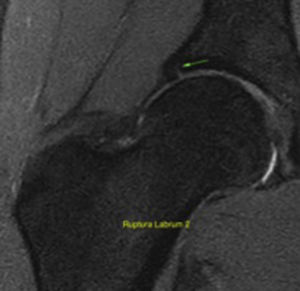

Para la evaluación de lesiones del labrum por medio de IRM como método de elección para identificar las lesiones de tejidos blandos alrededor de la cadera, incluyendo el labrum y el cartílago, se utilizó la siguiente clasificación simplificada: estadio 0 normal, 1 degeneración intrasustancial, 2 rotura parcial y 3 rotura completa.

En cuanto al tipo de CFA, la prevalencia fue de 22,5% (n = 18) para lesión tipo cam, y tanto para lesión tipo pincer como para la mixta fue del 1,3% (n = 1) (fig. 2). Las lesiones del labrum encontradas fueron del 33,8%, reportándose un 18,8% (n = 15) para la degeneración intrasustancial, para la rotura parcial del labrum 12,5% (n = 10) y para la rotura completa del labrum 2,5% (n = 2) (fig. 3). La prevalencia de lesión del cartílago femoroacetabular fue del 13,8% de las caderas evaluadas, encontrándose lesión del cartílago acetabular en un 6,3% (n = 5), porcentaje distribuido a su vez en un 5% (n = 4) con ablandamiento y edema del cartílago, y en un 1,3% (n = 1) con fisuras del hueso subcondral > 1,5 de diámetro; el 7,5% (n = 6) de la muestra presentó lesión del cartílago femoral. El quiste acetabular estuvo presente en el 5% (n = 4) de la población. La lesión de la unión condro-labral fue visualizada en un 10% (n = 8) y la sinovitis en el 1,3% (n = 1). Otros hallazgos encontrados fueron el edema de la cabeza femoral en el 5% (n =4), engrosamiento capsular o de ligamentos en el 2,5% (n = 2), coxa profunda en el 17,5% (n = 14) y el quiste labral o paralabral en el 1,3% (n = 1). Ningún jugador presentó quistes en la unión cabeza-cuello, alteración del ligamento redondo ni retroversión u Os acetabular.